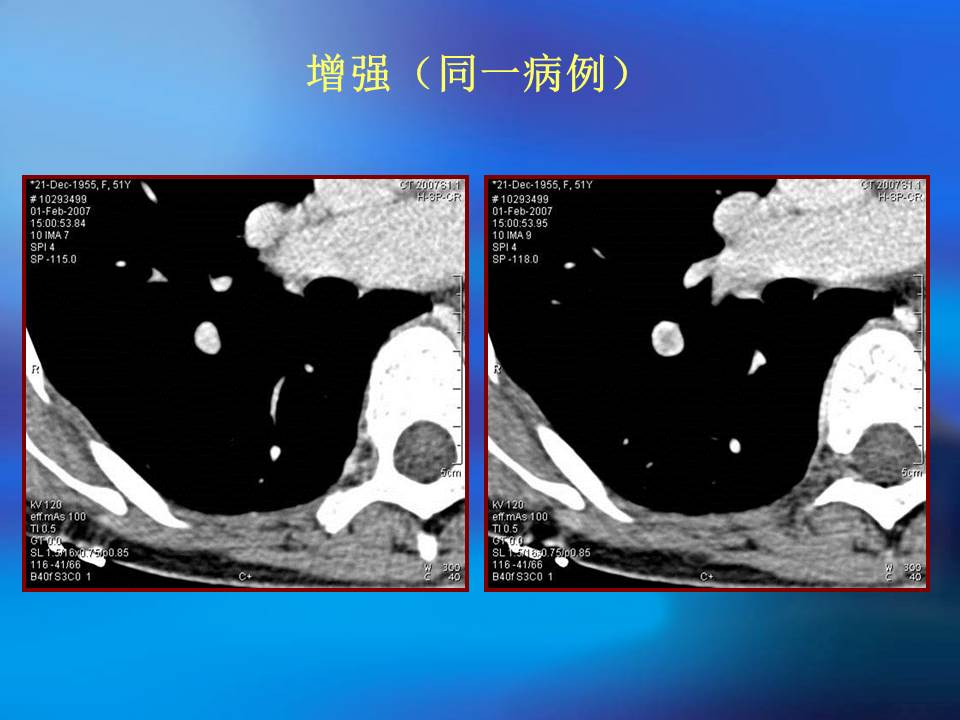

肺良性肿瘤